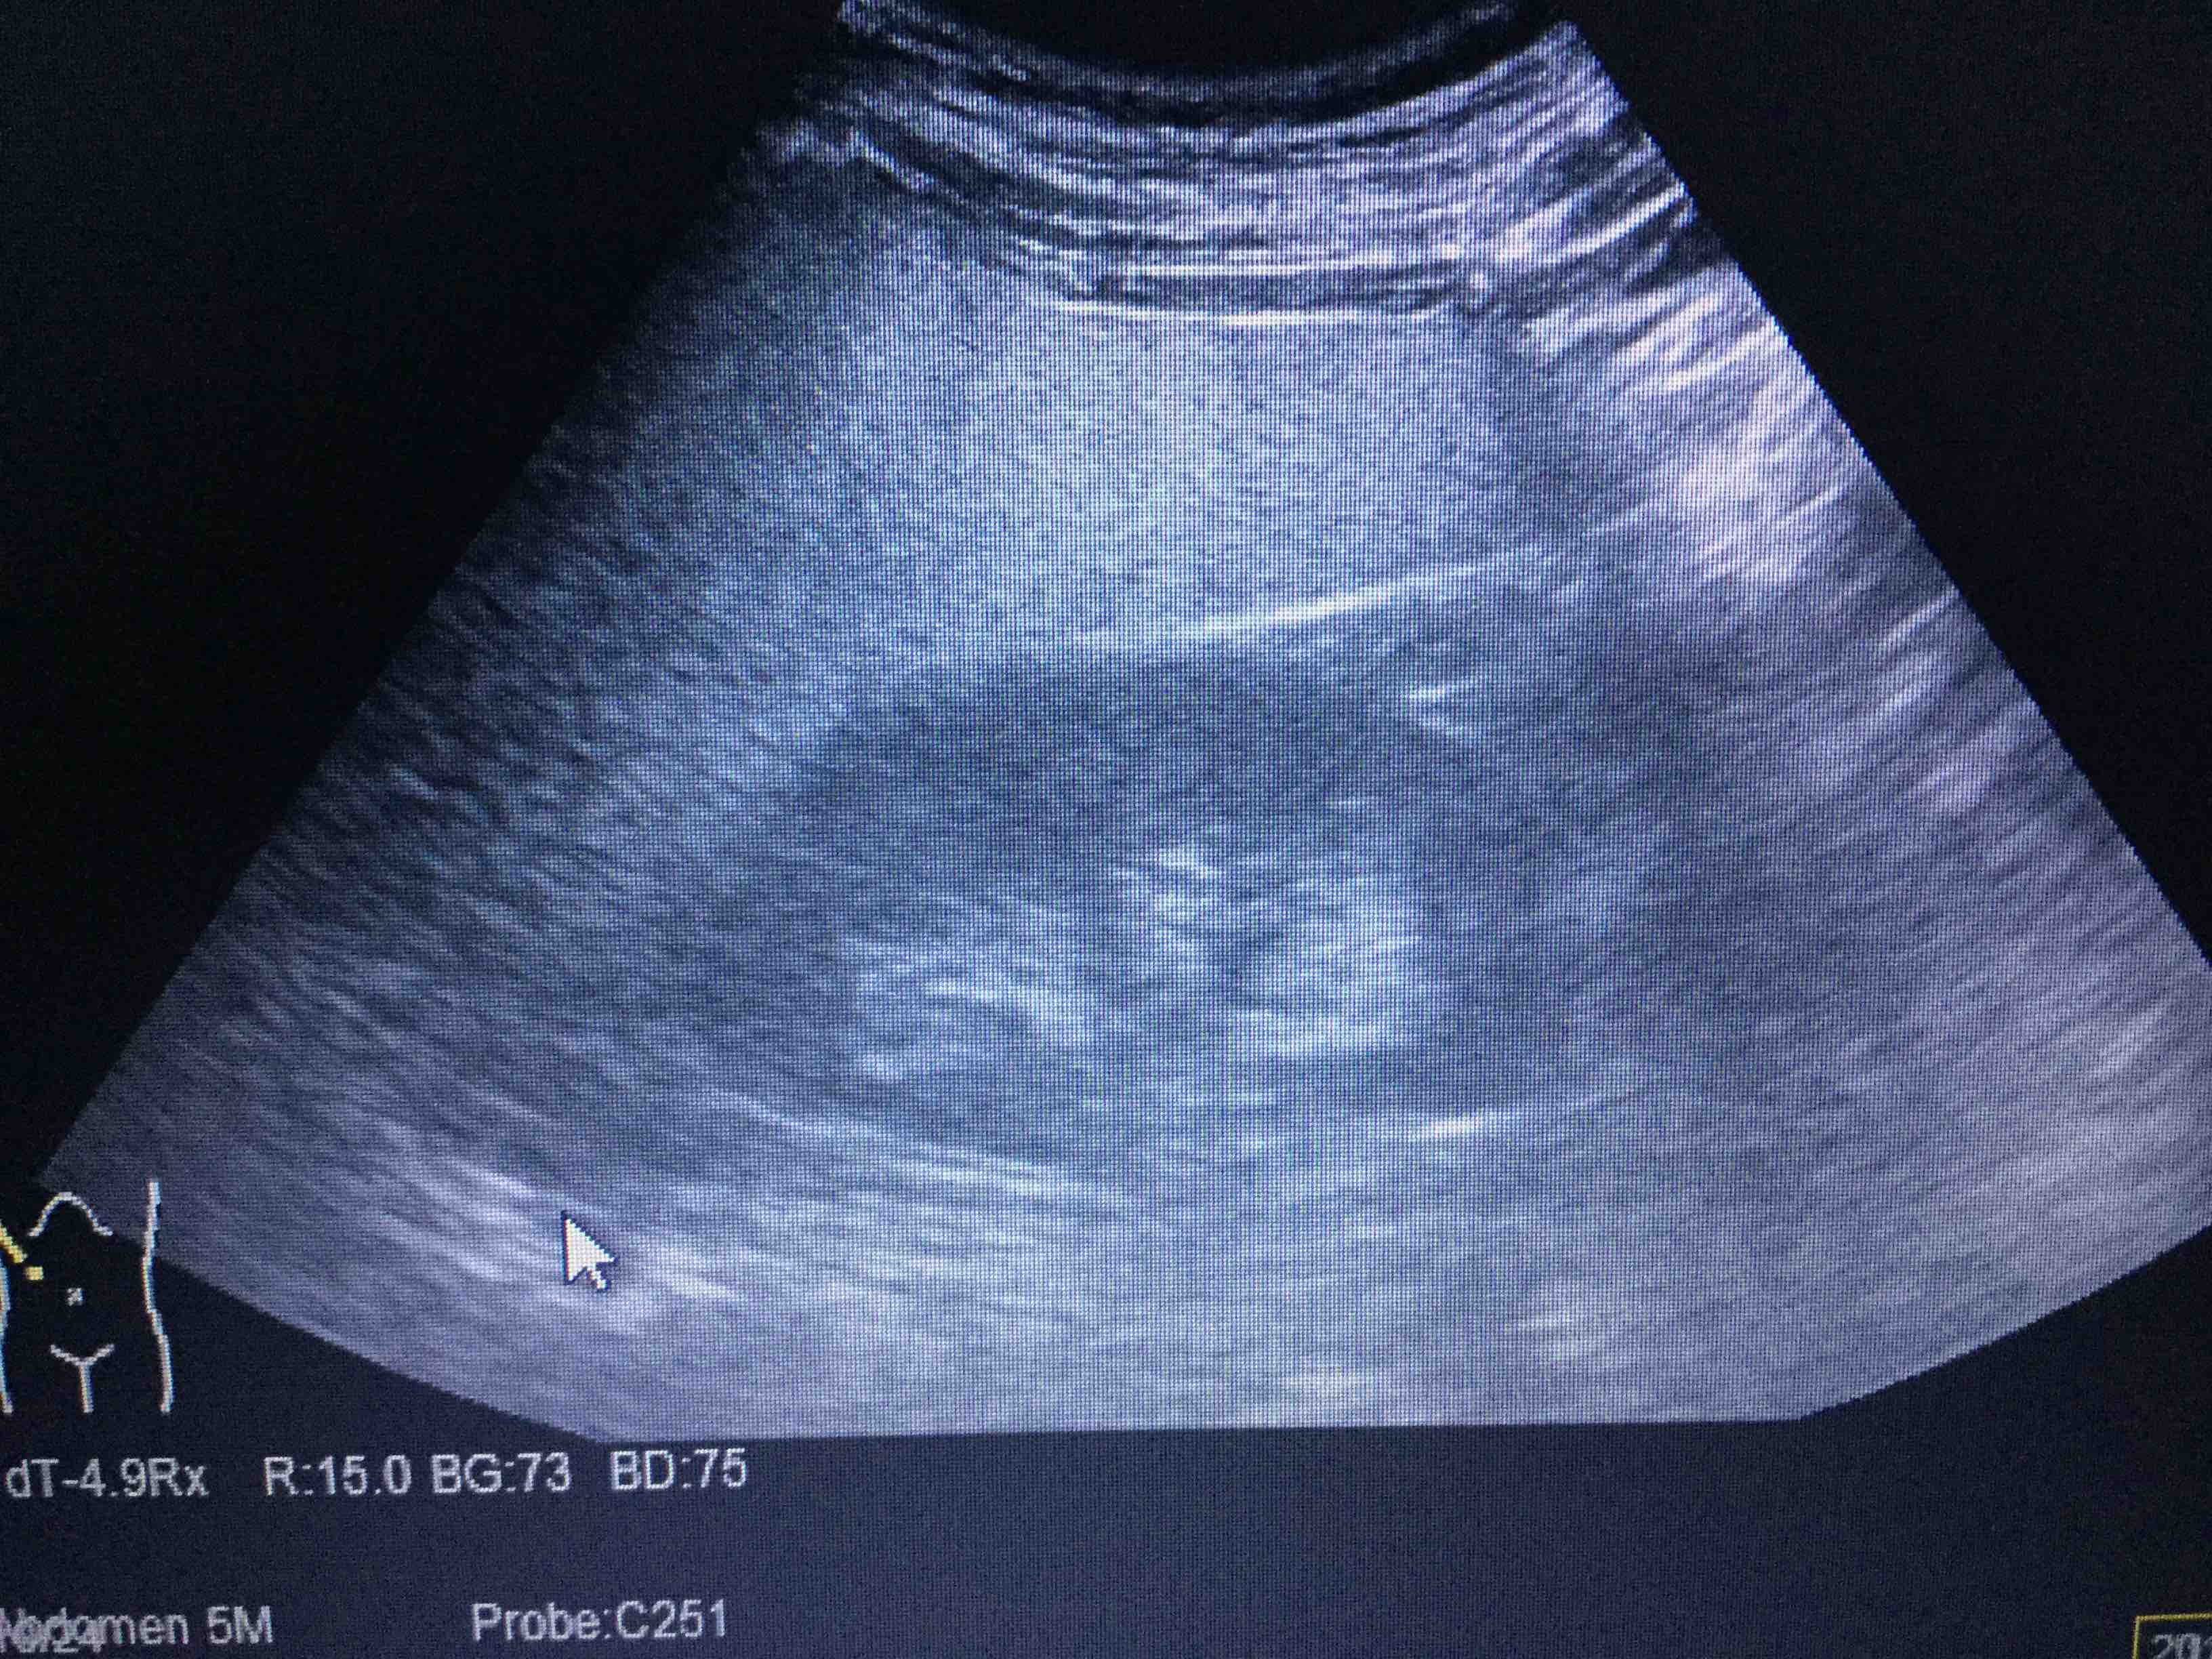

相馬医院 - 腹部エコ。

超音波検査で脂肪肝を,みて,見て,診よう 4。

写真中 脂肪肝−の方の腹部USあびこ内科外科大橋クリニック。